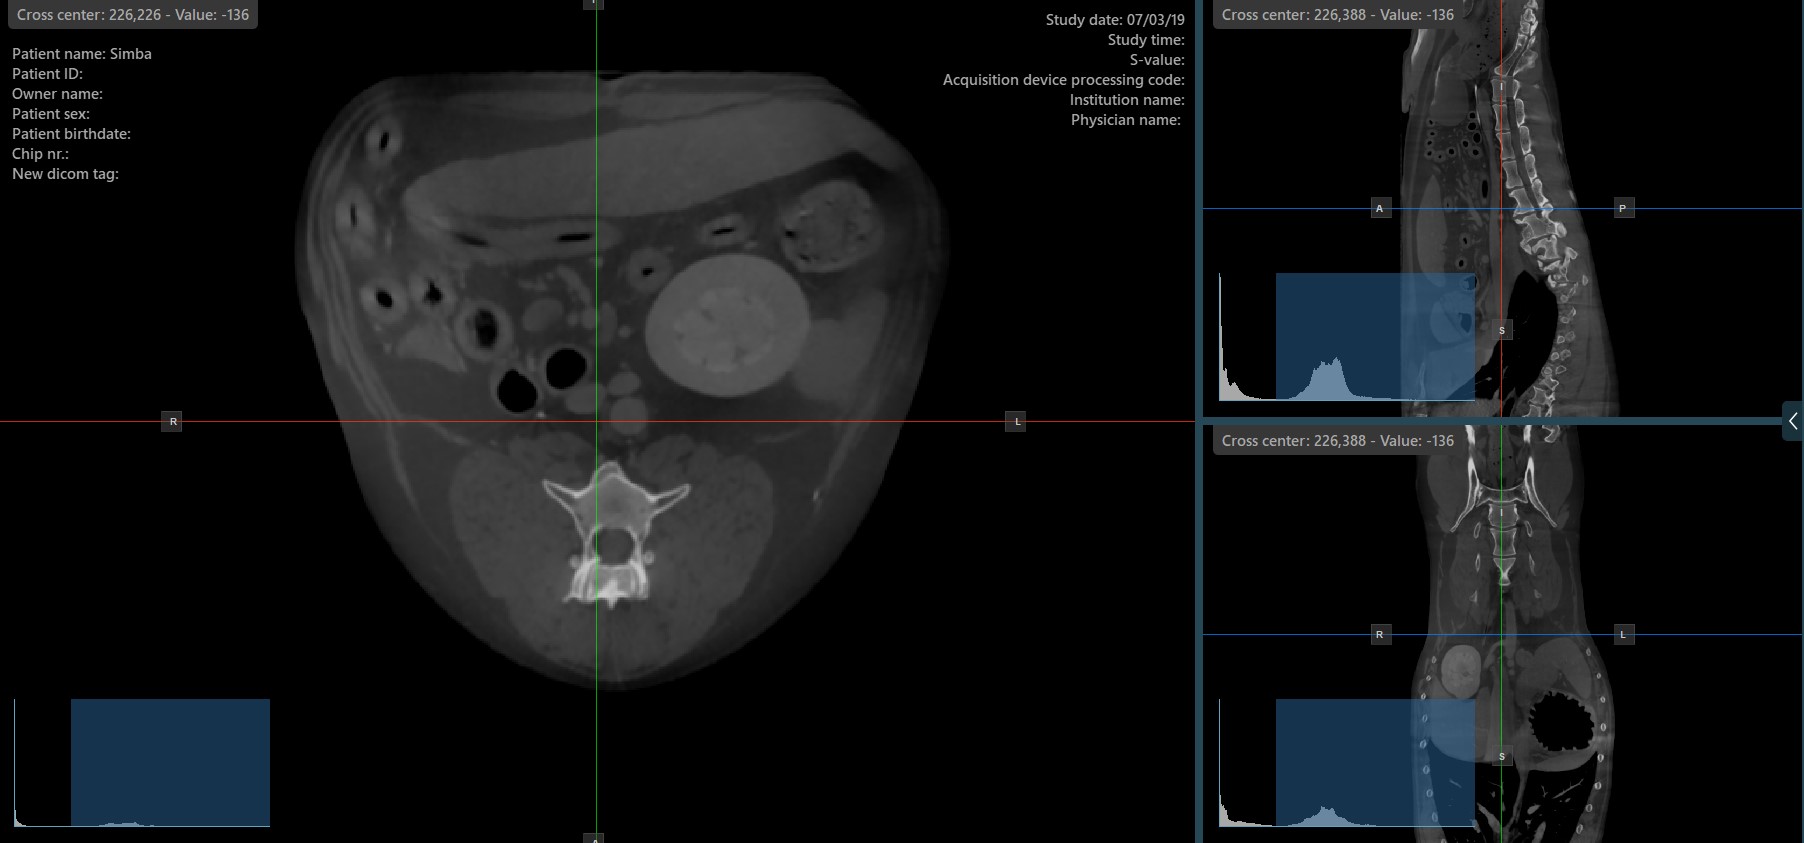

The slicers in MPR view show the intersections and orientation of the three image planes displayed in the active viewports. Users can modify the slicers and change the cross-sectional position of the slices based on the 3D volumetric data.

Each slicers is distinguished by their specific color, which representes the image plane:

The blue slicer marks the axial plane of the object (perpendicular to the ground)

The red slicer marks the coronal plane (parallel to the ground)

The green slicer marks the sagittal plane (perpendicular to the body)

Show/Hide Slicers¶

By default, the slicers are visible on the top of the images. The corresponding icon in the left toolbar of the CT Viewer will be selected when the slicers are visible.

Press the Hide/Show Slicers icon the left toolbar to hide the slicers. The corresponding icon in the left toolbar of the CT Viewer will be deselected when the slicers are hidden.

Users can toggle the visibility of the slicers by using the Hide/Show Slicers option from the left toolbar, or using one of the Tools -> Hide Slicers or Tools -> Show Slicers options from the CT Viewer menu.